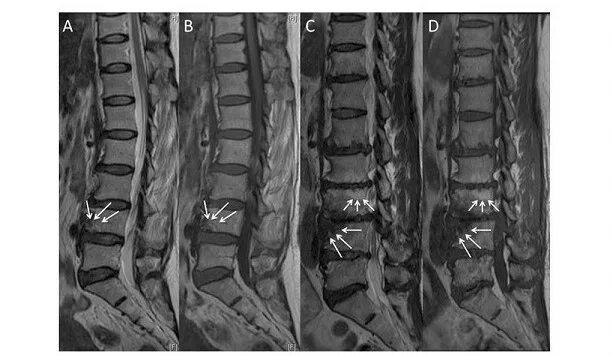

Modic тип 1